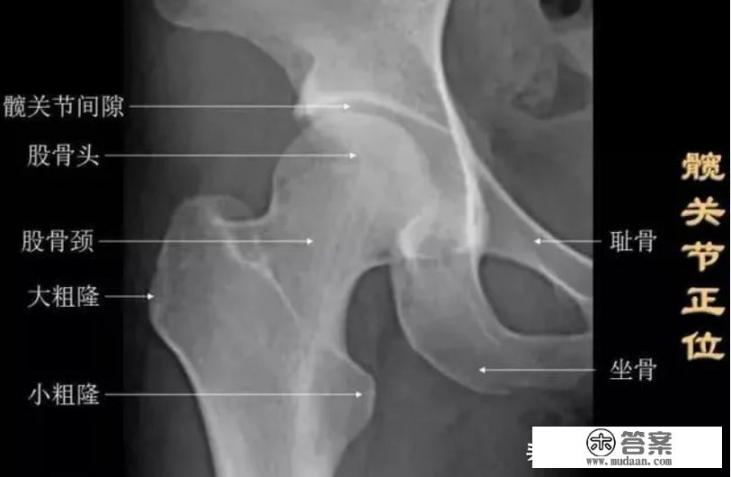

常规拍片,都会拍髋关节单侧,比较分辨率高,观察病灶细致,也可以看到发育的情况,根据人天生或者后天的改变而变化。下图就是X线检查,标记好解剖部位,清晰看到髋关节周围一些解剖是叫什么,才知道髋关节有哪些功能?

常规拍摄正位片和侧位片。正位线片上,因髋臼三骨之间以“Y”形软骨相连,融合之前,表现为横行带状透亮影,其宽窄随着年龄变化而改变。年龄越小此透亮带越宽;年龄越大,透亮带变窄,15~17岁左右消失。股骨头大部套在髋臼内,表面光滑,为致密的细弧线。头的中心偏后下部有一小凹陷,是股骨头凹,有时可投影到股骨头弧线内侧,显示为小环形透亮圈。侧位片上,中央的凹窝是髋臼,呈半圆形的致密线。